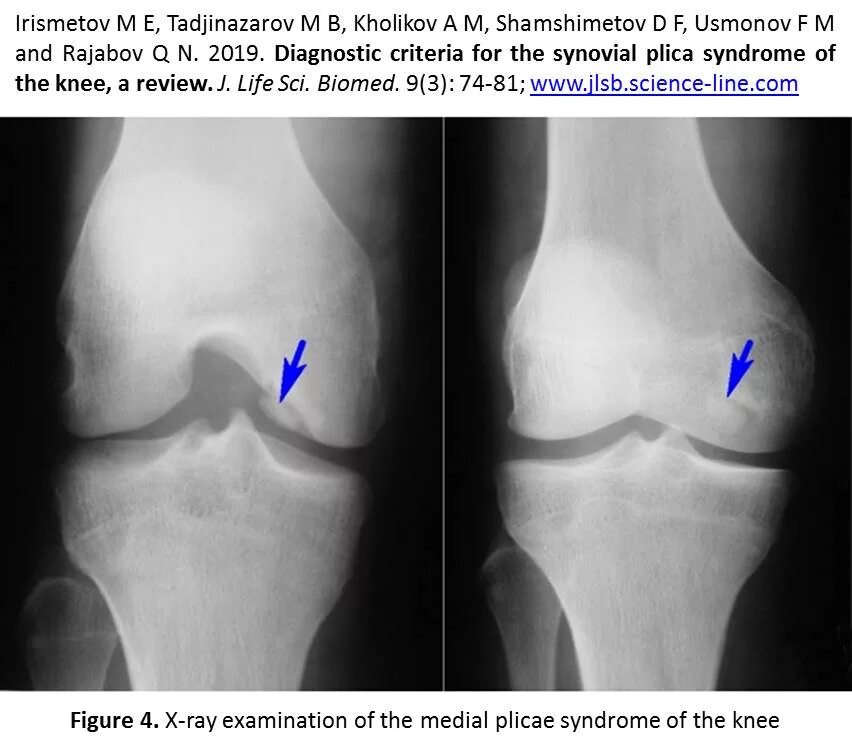

Что такое остеофиты коленного сустава как лечить